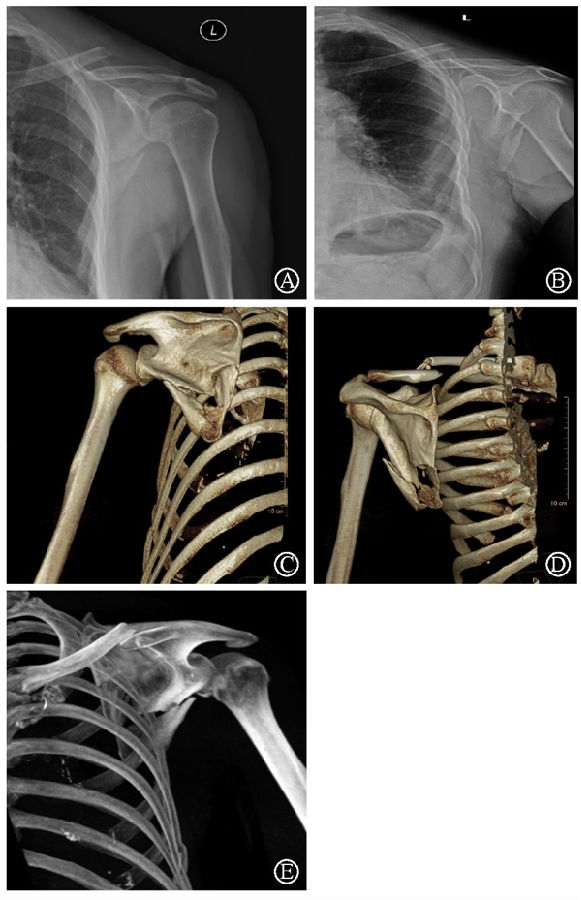

病例3为66岁老年女性患者,主因高处坠落伤导致左锁骨、左肩胛骨、左胸第5-6肋骨骨折。患者锁骨骨折和肩胛骨下缘骨折干扰冈下肌和肩胛下肌肌力,使肩关节稳定性受影响(图17)。

针对本例患者肩胛骨体部骨折,在术中采用术前设计好的缝线辅助固定技术(图18)。术后CT三维重建显示骨块复位满意,固定良好(图19)。

图17 术前X线片及CT三维重建示肩胛骨骨折累及肩胛颈及肩胛骨体部 图A-B:术前肩关节正位及出口位X线片;图C-E:术前CT三维重建